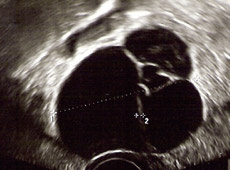

Abb. 2

Eierstockzysten: Mehrkammerige Zyste des Eierstockes im Ultraschallbild